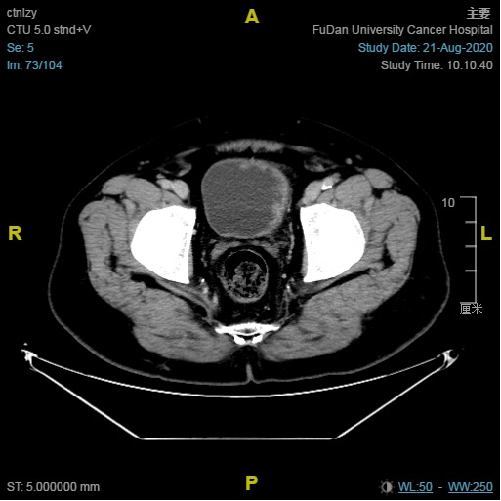

沈益君教授介绍了膀胱癌pd-l1表达的流行病学研究进展,中国膀胱癌的